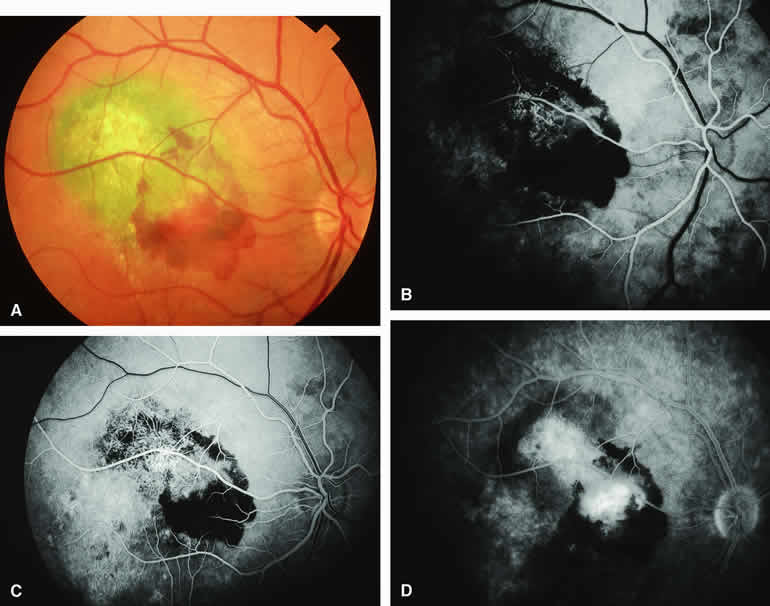

Choroidal Nevus Versus Melanoma with Choroidal Neovascular Membrane

A choroidal neovascular membrane occasionally develops from the surface of a small melanocytic choroidal tumor (nevus versus melanoma).12 This vascular structure can usually be anticipated because of the presence of ophthalmoscopically evident hemorrhagic or exudative subretinal fluid overlying a portion of the tumor (Fig. 8A). Fluorescein angiography in such cases (see Fig. 8B to D) generally reveals the neovascular membrane as a relatively well-defined vascular network that fluoresces brightly in the early frames of the study and leaks progressively by the late frames. If the subretinal fluid is grossly hemorrhagic, ICG angiographymay show the choroidal neovascular network better than does fluorescein angiography.